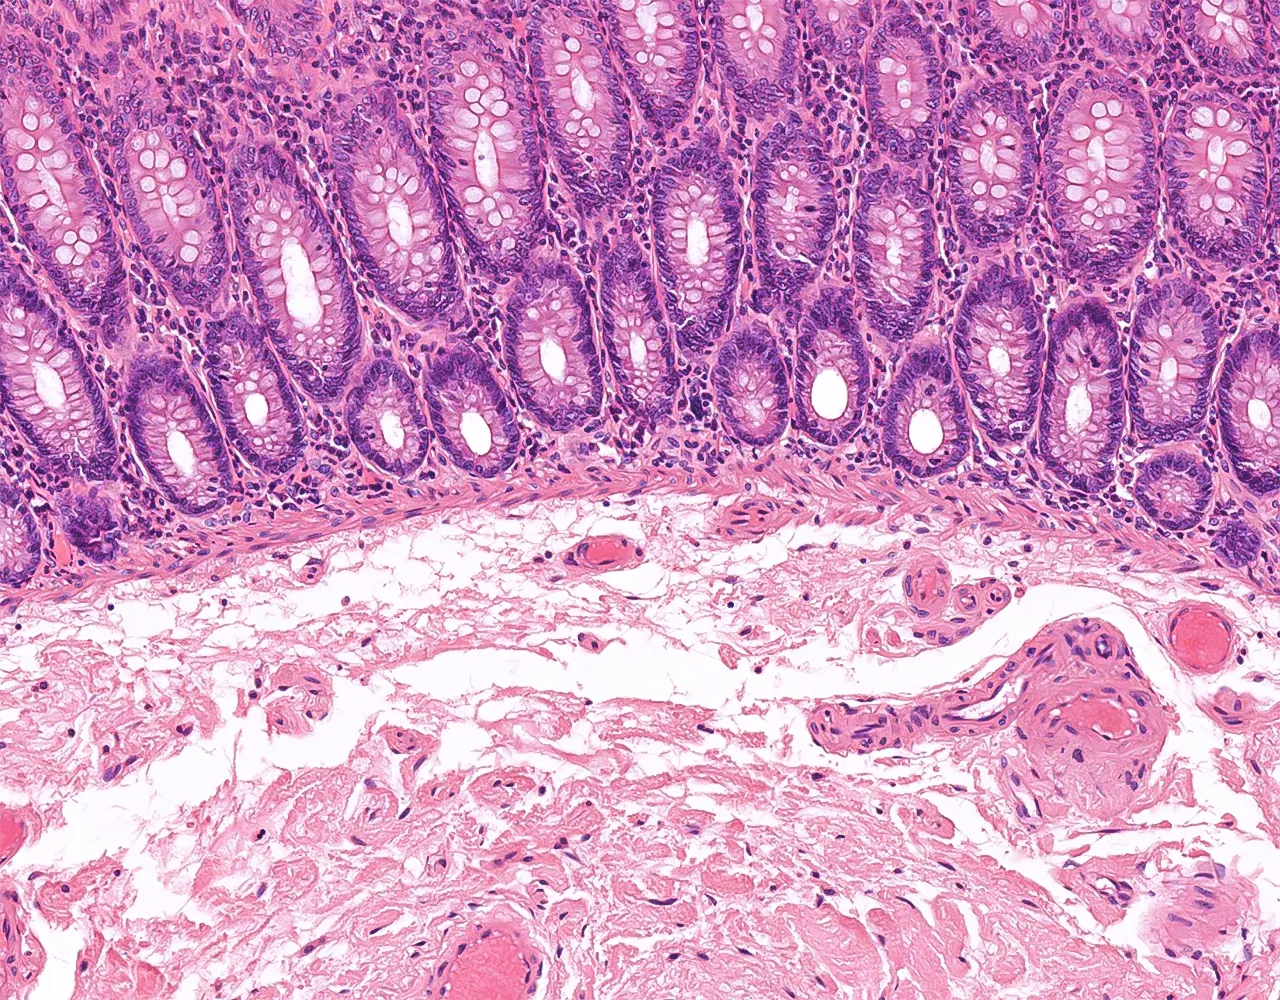

- Le gros intestin est responsable de l’absorption de l’eau et des électrolytes, de la sécrétion de mucus pour la lubrification, de la compaction et du stockage des matières fécales, ainsi que de la contribution aux interactions entre l’hôte et le microbiote.